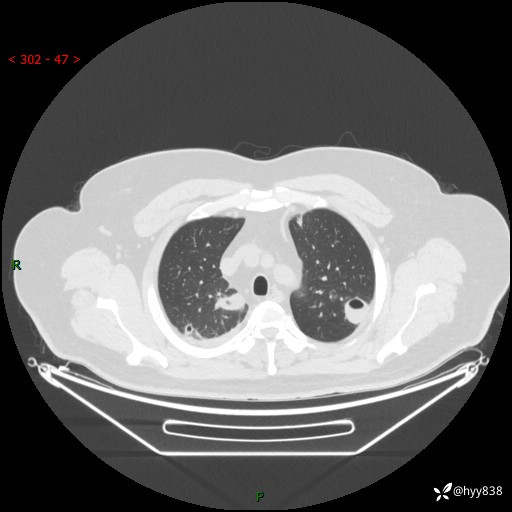

病例信息

性别:男

年龄:48岁

简要病史:发热来诊(门诊病人)

胸部CT平扫